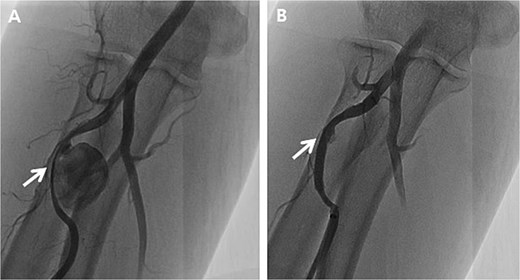

Pre-operatively, a modified Allen test was performed to verify sufficient blood flow to the hand through the ulnar artery in case of radial artery ligation. As a result, the test was positive indicating the ulnar artery had sufficient blood flow. Although the patient underwent the resection of both RAPs, the severely damaged radial artery was inevitably sacrificed (Fig. 4).

Intraoperative images and pathological specimens after the resection of pseudoaneurysms. (A) Distal lesion which was arterial catheterization site; (B) proximal lesion which was not related to arterial catheterization site; (C) the wall of pseudoaneurysm and hematoma (resected); (D) covered stent (removed).